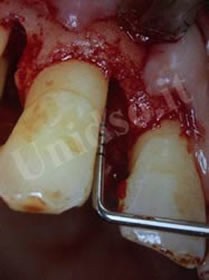

L’ Unità Operativa di Parodontologia e Igiene Orale si compone di 5 sezioni. L’attività’ clinico-assistenziale è svolta da diversi odontoiatri, supportata da igienisti dentali e assistenti alla poltrona, ed è articolata sulla base di appuntamenti programmati. Nell’Unità Operativa di Paradontologia e Igiene Orale del DSMOB si eseguono le seguenti prestazioni odontoiatriche: istruzioni d’igiene orale, ablazione tartaro, full radiografico, terapia dell’alitosi, levigatura radicolare, chirurgia parodontale riparativa, resettiva e rigenerativa e chirurgia plastica dei tessuti molli parodontali.